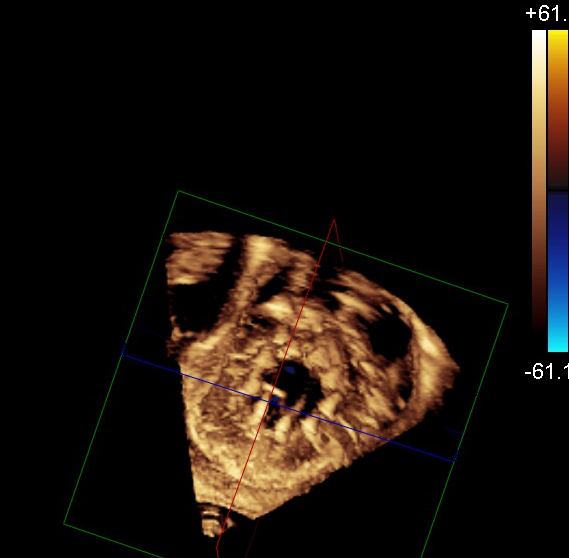

„Jak dotąd najczęściej stosowaną przez nas formą terapii był zabieg polegający na wprowadzeniu przez nakłucie żyły udowej specjalnych zapinek umożliwiających połączenie płatków, co poprawia ich przyleganie i zwiększa szczelność zastawki. Zabiegi tego typu, określane mianem przezcewnikowej naprawy metodą brzeg-do-brzegu (ang. transcatheter edge-to-edge repair – TEER), wykonuje się na bijącym sercu pod kontrolą dwuwymiarowej i trójwymiarowej echokardiografii w czasie rzeczywistym (tzw. echonawigacja). Niestety, ze względu na niekorzystną anatomię nie wszystkie zastawki można skutecznie naprawić tą metodą. W przypadku zbyt dużego poszerzenia wymiarów zastawki i oddalenia od siebie jej płatków zastosowanie klipsów może nie przynieść spodziewanego efektu; dla takich chorych rozwiązaniem mogłaby być całkowita wymiana zastawki” – tłumaczą specjaliści.

Od długiego czasu trwały intensywne badania nad opracowaniem protez zastawkowych, które można byłoby wszczepić bez konieczności przeprowadzania operacji kardiochirurgicznej, zastępując tym samym uszkodzoną zastawkę trójdzielną. Pierwsza tego typu zastawka – EVOQUE (Edwards Liefesciences, Irvine, USA) została zarejestrowana w Europie pod koniec 2023 r. Zbudowana jest ona z płatków wszytych w samorozprężalną ramkę, która jednocześnie stanowi element mocujący zastawkę w sercu. Przed wszczepieniem całość zamocowana jest na sterowalnym systemie doprowadzającym, który umożliwia przeprowadzenie zabiegu z dostępu przez żyłę udową. Procedura wykonywany jest głównie pod kontrolą echokardiografii trójwymiarowej w czasie rzeczywistym (echonawigacja).

Od 2021 r. pracujemy już z systemami zaprojektowanymi specjalnie do naprawy niedomykalności trójdzielnej, które charakteryzują się większą precyzją i skutecznością. Mimo to duża część chorych nie spełnia kryteriów anatomicznych do założenia „klipsa”: pierścień zastawki jest zbyt poszerzony, a płatki leżą zbyt daleko od siebie, by dało się je zbliżyć i skutecznie uszczelnić zastawkę. Dla tej grupy przełomem stało się wszczepienie samorozprężalnej protezy EVOQUE drogą przezżylną. Dostępna w Europie od niespełna dwóch lat zastawka jest pozycjonowana pod kontrolą echokardiografii przezprzełykowej bez otwierania klatki piersiowej. Wypełnia lukę w tej dużej grupie chorych kierowanych do zabiegów naprawczych. Za jej pomocą będziemy w stanie leczyć pacjentów, którzy są objawowi, nie mają jeszcze zaawansowanych cech niewydolności prawokomorowej, ale z drugiej strony też już mają na tyle zaawansowaną wadę, że nie można jej naprawić za pomocą dotychczasowych metod przeskórnych.

Dr hab. n. med. Piotr Scisło, kardiolog zajmujący się echokardiografią, WUM:

Chronologicznie najpóźniej terapie przezcewnikowe znalazły zastosowanie w leczeniu niedomykalności trójdzielnej. Powodem była skomplikowana anatomia i obrazowanie zastawki trójdzielnej. Przełomem dla Polski stał się rok 2018, kiedy to zespół WUM wykonał pierwszą w kraju przezcewnikową naprawę zastawki trójdzielnej metodą brzeg-do-brzegu.

Ograniczenia anatomiczne sprawiają, że nie każdy chory jest jednak dobrym kandydatem do leczenia niedomykalności metodą brzeg-do-brzegu, potrzebna jest wymiana zastawki, a nie jej naprawa. Odpowiedzią na tę lukę stała się zastawka EVOQUE – pierwsza bioproteza do przezcewnikowej implantacji w ujście trójdzielne, która została dopuszczona do użytku w Unii Europejskiej w październiku 2023 roku.